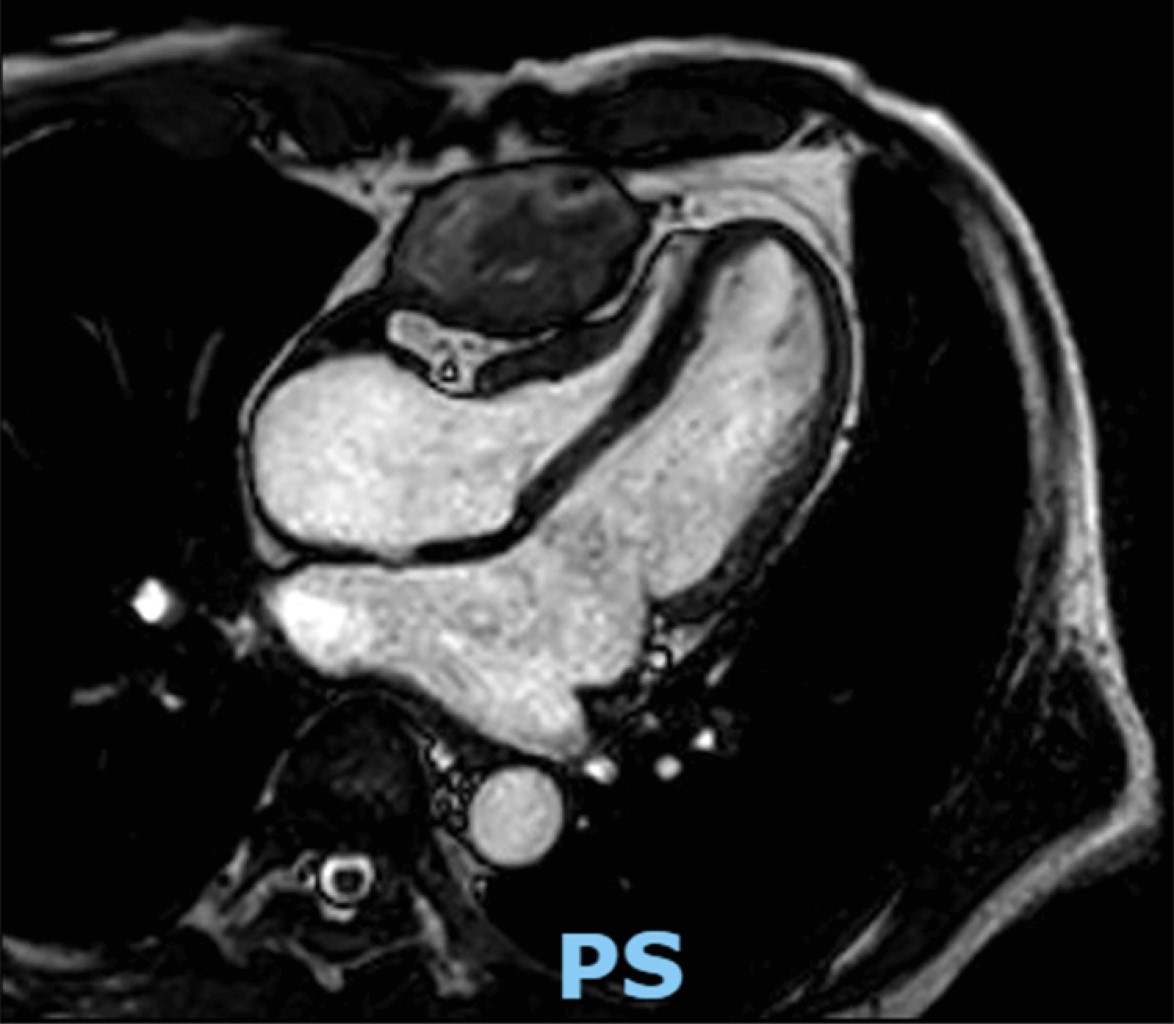

The MRI showed an intrapericardial lesion measuring 58.1 by 6.7 mm with irregular margins, heterogeneous in all sequences, predominantly hypointense. There was no contrast enhancement observed, and it showed compression of the right ventricle, restricting diastolic filling and limiting contractility (Figure 1).

The transthoracic echocardiogram demonstrated significant left atrial dilation, normal valves, with a systolic displacement of the tricuspid annular plane of 5, a left ventricular ejection fraction of 55%, a pulmonary artery systolic pressure of 46 mmHg, a right ventricle of normal diameter, with a fractional area change of 35%. A mass dependent on the pericardium causing extrinsic compression of the right heart chambers was evident.

In this patient without associated symptoms, the decision to perform surgery was based on the finding of constrictive pericarditis found in the MRI and the alteration of the functional class. The image of the unidentified mass on the anterior wall of the right ventricle, along with the calcified pericardium, reduced right ventricular filling, consistent with the diagnosis.

Figure 1